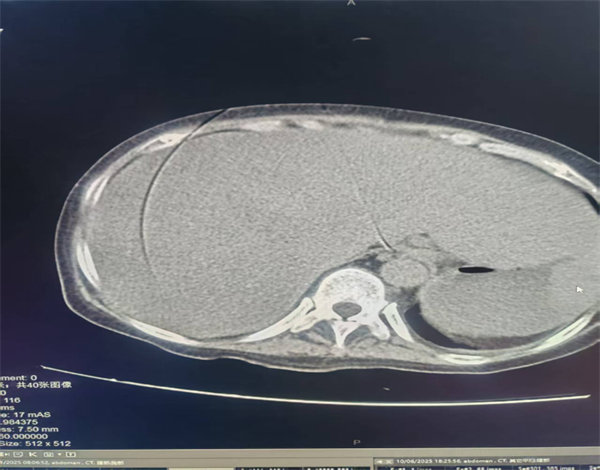

附图1、伪影图片

附图2、伪影图片